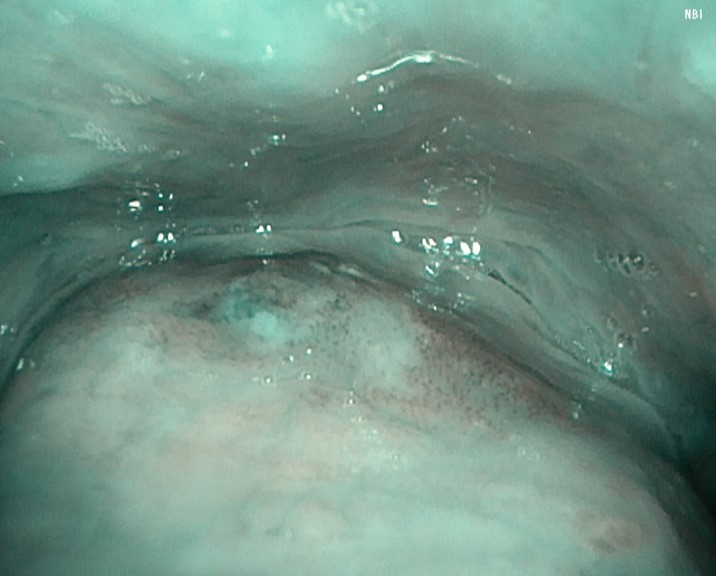

Case 3: Hypopharyngeal High-Grade Dysplasia

Under general anesthesia, the left pyriform sinus was observed after hypopharyngeal exposure. A well-defined brownish area with atypical microvessels was identified.

Compared with VISERA ELITE OTV-S190, VISERA S OTV-S500 demonstrated reduced color and luminance unevenness due to noise reduction processing, improved depth of field, and sharper edge definition, resulting in clearer visualization of the lesion.

NBI Image

Video System Center: VISERA ELITE OTV-S190

Video Rhinolaryngoscope: ENF-VH

Video System Center: VISERA S OTV-S500